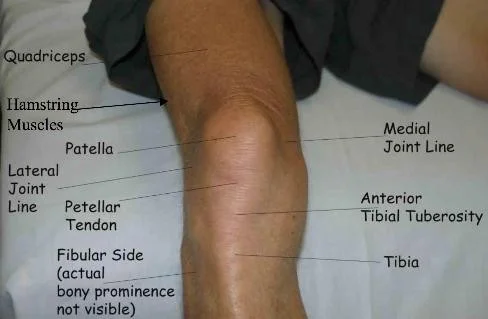

Tenderness

- Generalized: to start with

- Specific points:

- Quadriceps muscle

- Patella

- Patellar tendon

- Tibial tuberosity

- Joint lines: medial/lateral

- Collateral ligaments

- Head of Fibula

- Popliteal fossa

- Hamstrings

Knee - Medial Structures

- Tibial Tuberosity

- Joint Line

- Medial Tibial Condyle

- Patella

- Medial Femoral Condyle

- Joint Space - The space between the Medial Femoral Condyle and Medial Tibial Condyle

- Medial Collateral Ligament (MCL)

Knee - Lateral Structures

- Quadriceps

- Patella

- Tibial Tuberosity

- Head of Fibula

- Lateral Collateral Ligament (LCL)

- Lateral joint line

- Bone: landmarks (Patella, Tibial Tuberosity, head of Fibula) tenderness, mass, crepitus

- Joint lines: anterior, medial, lateral